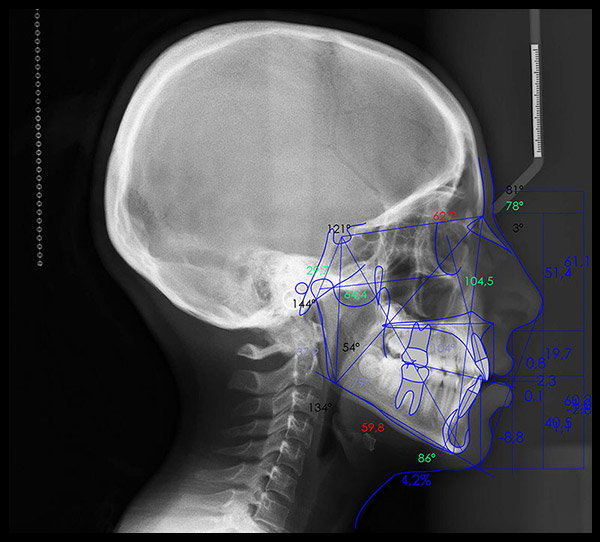

Ofrecemos la más alta tecnología con una atención profesional y personalizada por parte del equipo altamente calificado en donde contará con el mejor estudio para sus pacientes.